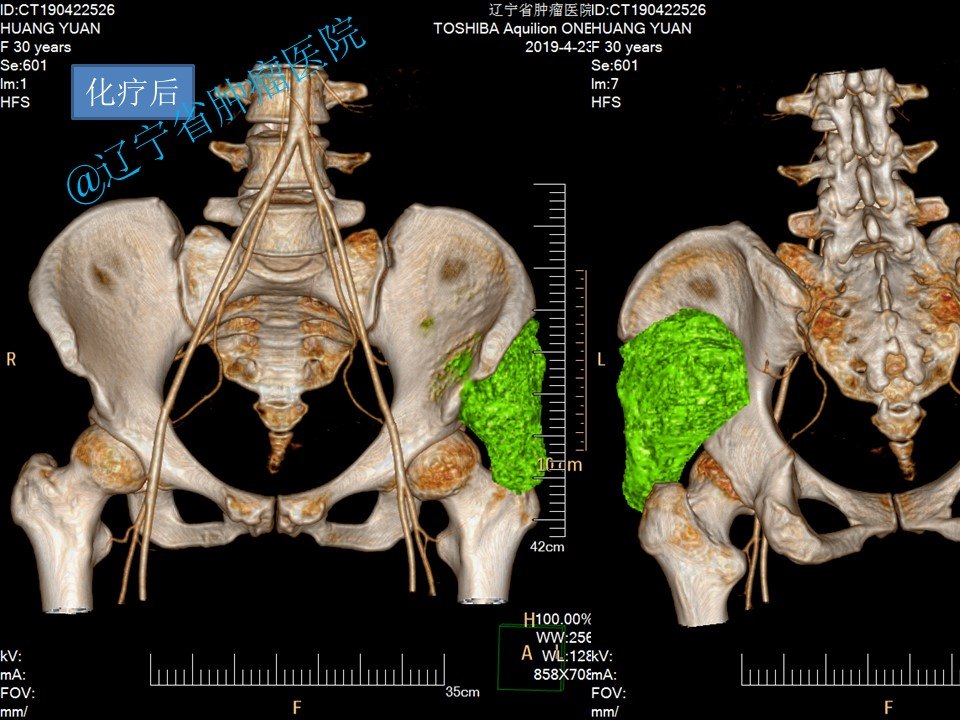

请问右髂骨是哪个部位?右髂骨在哪?[s0]右侧髂骨图[s1]1,右侧髂骨骨折;2.2,左[s2]患者的临床表现及辅助检查结果,诊断为右髂骨骨折,遂将患者收入我科。二、治疗经过入院后,与患者及家属进[s3]1,右侧髂骨骨折;2.2,左[s4]右侧髂骨在哪个位置示意图[s5]右侧髋臼及髂骨病变.[s6][已会诊] 右侧髂骨占位性病变[s7]右侧髂骨 来自网易[s8]右侧髂骨 来自网易[s9]右髂骨骨折术后切口不愈合二个月[s10]镜湖答疑跑步后膝盖疼怎么办运动时候髋关节疼怎么办练普拉提后髂骨疼[s11]右侧髂骨 来自搜狐网[s12]右髂骨翼骨折用手术吗?[s13]骨盆多发骨折:骨盆x线片及骨盆ct平扫可见右侧髂骨、右侧耻骨上下支多发骨质中断[s14]右侧髋臼及髂骨病变[s15]右侧髂骨 来自搜狐网[s16]从片子和触诊上看,她的诊断结果是这样的:右侧髂骨比较严重外旋,左侧[s17]右髂骨在哪腰部以下臀部以上的骨头就是髂骨,所以右髂骨在髂骨右侧。髂[s18]骨二科持续运用新技术普惠广大患者[s19]陈大哥因外伤导致右髂骨骨折,保守治疗效果也很好![s20]右侧髂骨 www.cn-healthcare.com[s21]【典型案例】骨盆、右髂骨、右坐骨骨折[s22]妻子患病髂骨占位——跪求!!大家帮看看长了什么东西[s23]右侧髂骨 个人图书馆[s24]【原创】右髂骨病变,有病理,一周后公布。[s25]。骶骨还有没有骨折?不太明显;左侧髂骨翼也不太像骨折。ct证实一下。[s26]右侧髂骨 搜狐网[s27]患者为高处坠落伤,左侧骨盆髂骨翼及髋臼前后柱粉碎骨折。这类损伤对患者致残率高,又因其解剖结构原因,周[s28]《上海髋撞就诊经历—待术中》4[s29]右侧髂骨慢性骨髓炎[s30]右侧髂骨 来自网易[s31]右侧髂骨 知乎[s32]本人首例 改良stoppa 髂骨窗入路 治疗髋臼骨折[s33]右侧髂骨 www.haodf.com[s34]图片[s35]3D REC (13).jpg[s36]法斗右腿髌骨脱位救救孩子吧[s37]左侧髂骨粉碎性骨折、右侧耻骨上下支骨折[s38]左髂骨粉碎性骨折,骶1,2椎体骨折,左侧耻骨上下支骨折,耻骨联合分离[s39]